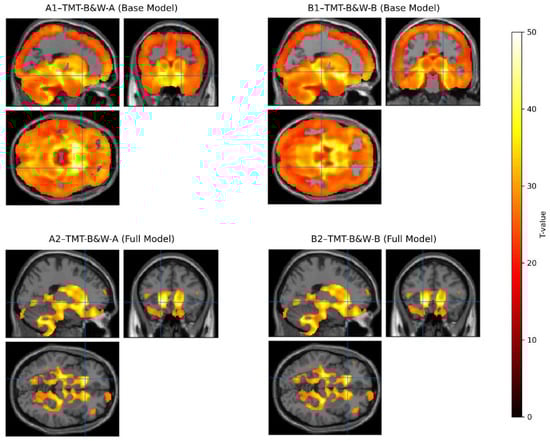

| Model | Peak MNI (x, y, z) | Cluster Size (Equivk) | Peak T | Anatomical Region |

|---|---|---|---|---|

| TMT-B&W-A | ||||

| Base | 19.5, 19.5, −13.50 | 515.60 | 42.64 | Right Orbitofrontal Cortex * |

| + Age + Edu + gender + TICV | −19.5, 25.5, −4.50 | 594 | 8.05 | Left Thalamus * |

| TMT-B&W-B | ||||

| Base | 19.5, −24, −7.50 | 515.50 | 50.65 | Right Insular Cortex * |

| + Age + Edu + gender + TICV | −19.5, 25.5, −4.50 | 621 | 8.11 | Left Thalamus * |